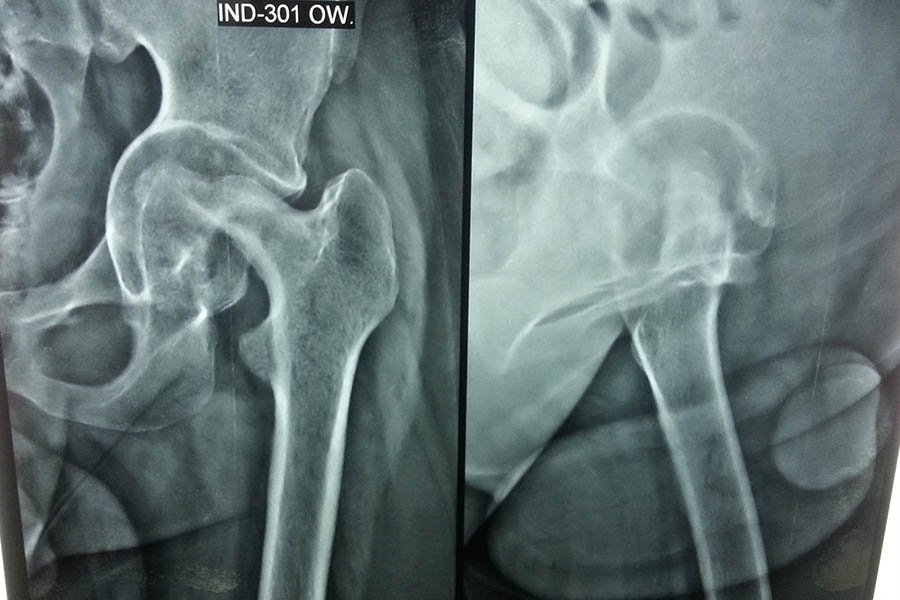

Total Hip Replacement

Case 1